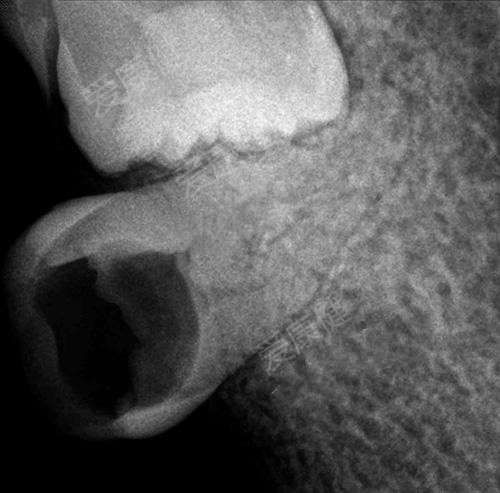

(拍片檢查需要做根管治療)

5、蛀牙惡化階段2——根尖周炎

當你牙齒疼得要命,甚至臉部開始腫脹時,你依然強撐著說:“沒什麽(me) 大不了的,不就是一顆牙齒,我吃止痛藥就行了!”

你可別再開玩笑了!現在蛀牙已經引起根尖周炎,容易引發感染,甚至嚴(yan) 重的話會(hui) 危害身體(ti) 健康!此時建議到正規醫療機構檢查,並對症處理!